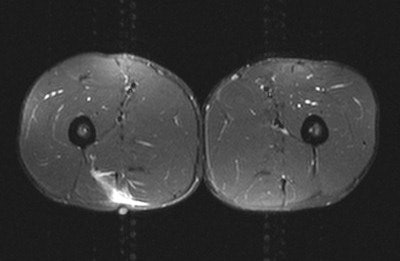

"There is a great debate about when best to image soft-tissue injuries. The athlete wants it immediately or at least within 24 hours. In my experience, it's better to wait between 24 and 48 hours because otherwise there's a high risk of having a false negative," stated Healy, who helps look after players from several Premiership and Championship football clubs, as well as Premiership rugby union teams, and has been involved in a Champions League thigh-muscle injury study since 2007. "If the imaging does not correlate with the clinical findings, then it's very important to repeat the imaging. Often, if you image too early, then you'll miss the extent of what's going on."

He has a simple rule about which modality to use: If the patient points to the abnormality with one finger, start with an ultrasound, but if the patient points to it with a hand, go straight to MRI. Also, ultrasound is better for imaging superficial structures, while MRI is better for deep structures.